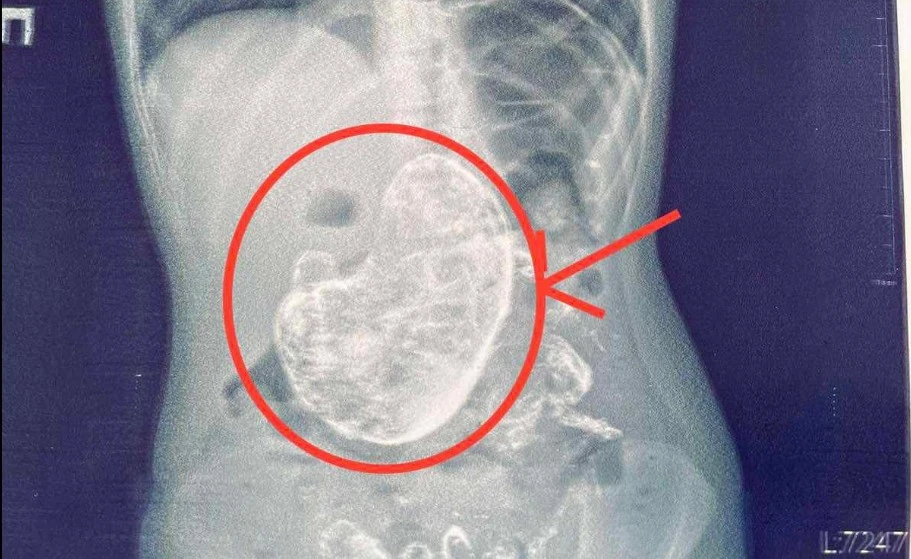

В Івано-Франківську лікарі обласної дитячої лікарні прооперували 6-річну дівчинку та видалили з її шлунку кілограм волосся.

"Rtg дослідження шлунково-кишкового тракту допомогло виявити стороннє тіло в шлунку, а ФЕГДС підтвердила наявність тріхобезоару", – пояснює Тарас Мельник.

Завдяки злагодженій роботі команди гастроентерологів, анестезіологів і хірургів дитину успішно прооперували, а стороннє тіло, сформоване з волосся вагою 1 кг, видалили.